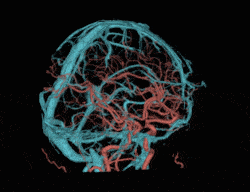

基于AI技术,对搏动的冠脉进行精准的识别、追踪、运动建模和运动伪影校正